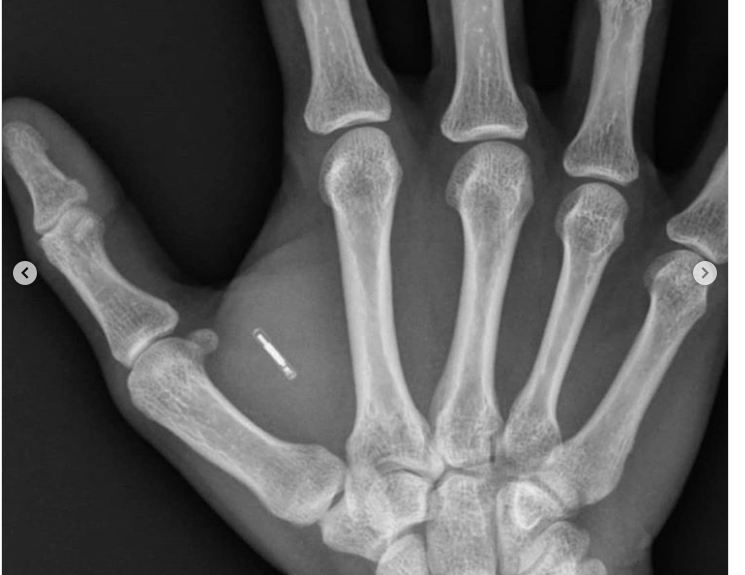

Lebih Dari 4000 Orang di Swedia Memasang Chip Di Tangan, Begini Penampakannya